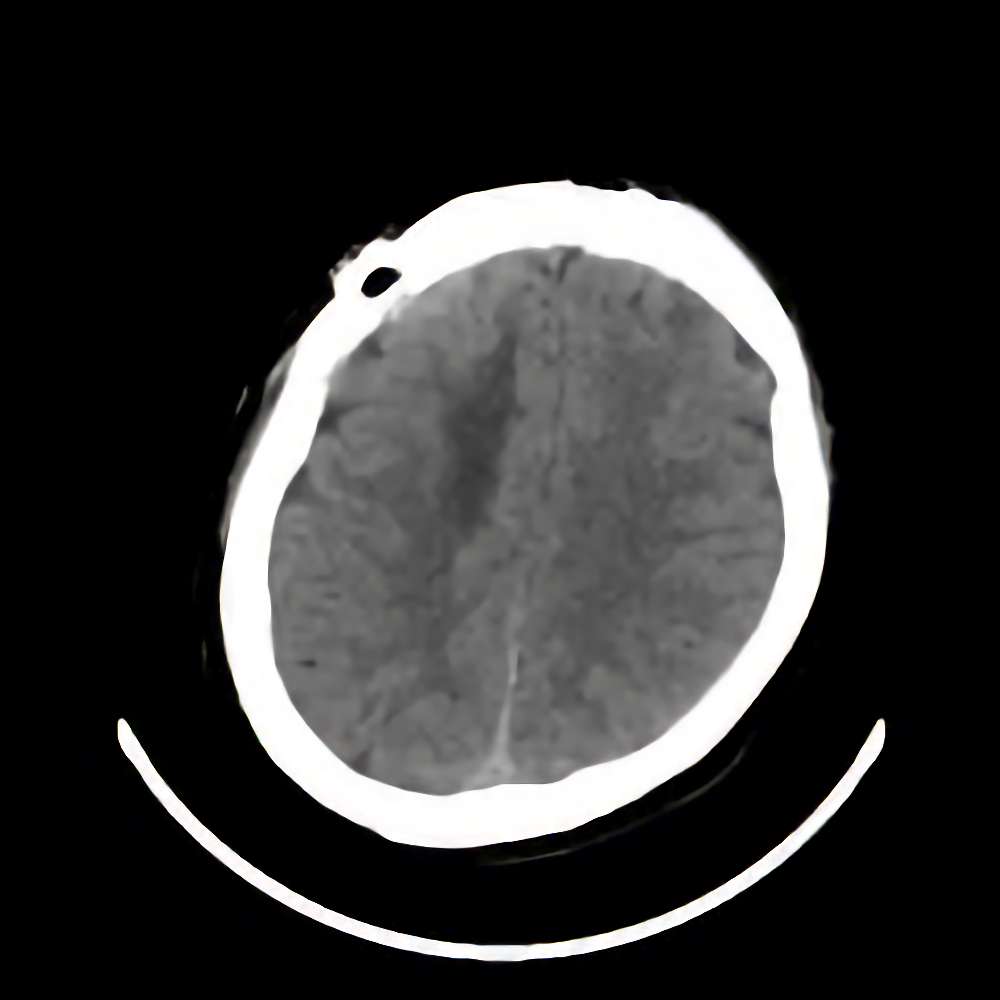

脳腫瘍

断層撮影

手術前1

No.’13_186 手術前1

No.’13_186 手術後